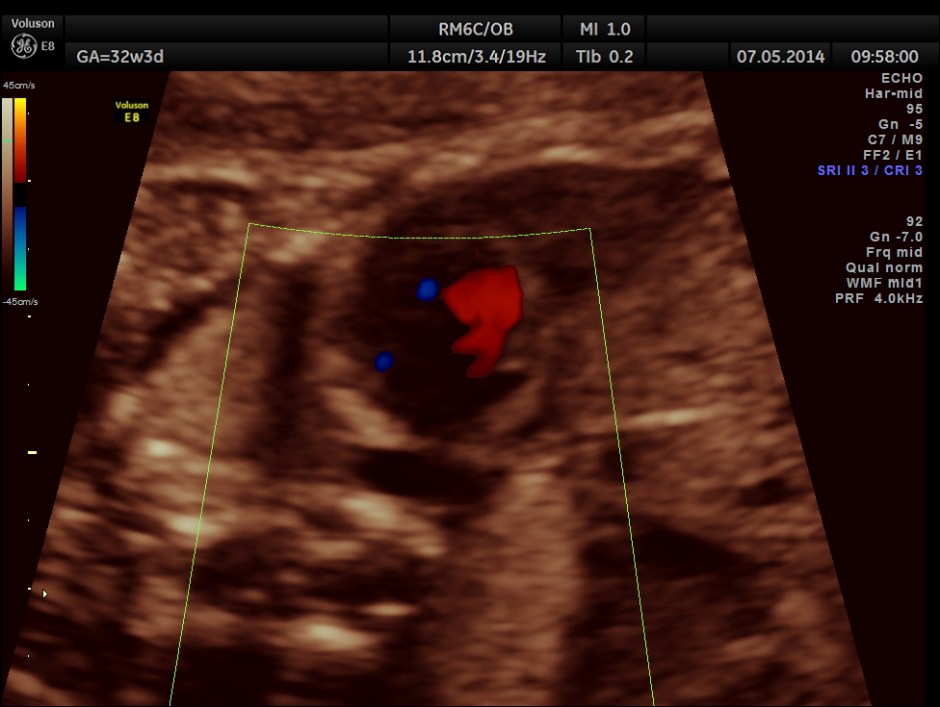

Ductal arch is prominently dilated in comparison to the aortic arch and there appears to be a flow reversal also.

3 vessel view also shows the pulmonary artery to be bigger in size than the aorta.

No definitive pulmonary vein draining into the left atrium could be made out . A common transverse vessel was seen beneath the left atrium . The LA & RA were smaller than the RA. Similarly the Aorta and the aortic arch were smaller than the pulmonary artery and the ductal arch due to the increased flow in the right side.